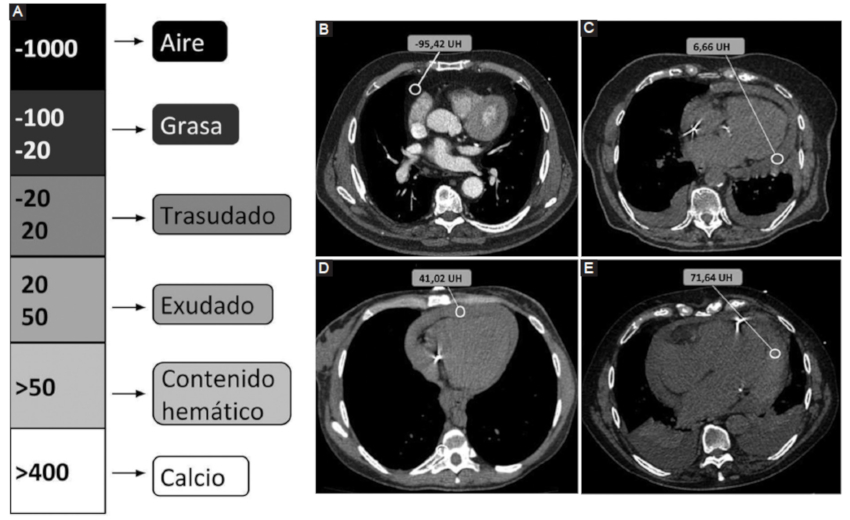

Por su parte, el análisis de la densidad del DP resulta una herramienta complementaria útil y accesible. Se ha estudiado la composición del DP por medio de la medición de densidades tomográficas y su correlación con los datos del análisis bioquímico. En este sentido, una densidad promedio similar a la del líquido es indicativa de trasudado, mientras que valores mayores a 20 UH se vinculan con exudados y mayores a 50 UH con contenido hemático con alta especificidad (Fig. 1) (3,7.